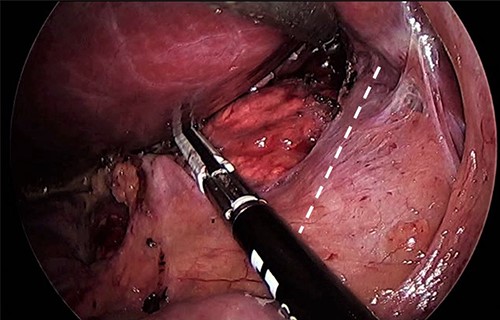

As for the LRA, ports are inserted in similar fashion as the LLA but with more to the right side. An additional port at the right midclavicular line is an optional (Fig. 5). In Patient 1, we started with the LLA to control the blood pressure caused by the adrenal gland and to prevent unnecessary bleeding from occurring. Conversely, we started with LSG in Patient 2 because the priority was controlling his comorbidities by weight reduction. The right hepatic lobe was retracted to expose the subhepatic area. The right hepatic ligaments were released, exposing the inferior vena cava. Dissection lateral to the IVC was continued exposing the right adrenal (Fig. 6). Complete dissection of the adrenal gland was completed and the pedicle was controlled using energy device (Fig. 7). There was constant communication with the anesthesia team during the surgery. After complete dissection of the adrenal gland, it was placed in the endobag and the LSG was conducted similar to the above-mentioned steps (Fig. 8).